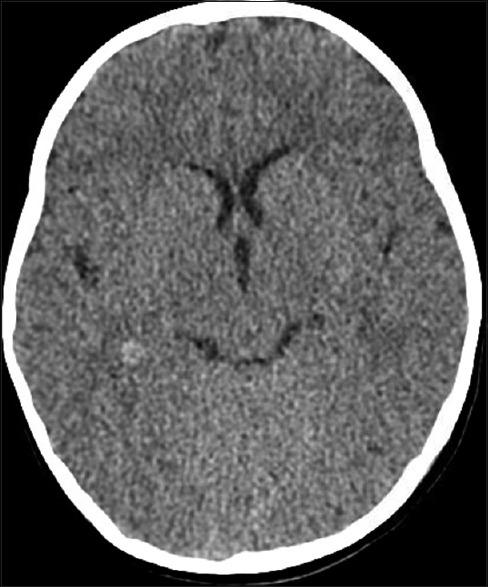

Choroid plexus tumors (CPT) in the pediatric population are usually discovered in symptomatic patients often with symptoms of increased intracranial pressure, with hydrocephalus as the most common presentation, along with seizures, subarachnoid hemorrhage, or focal neurological deficit. Most CPTs are found to be benign choroid plexus papillomas (CPP), whereas a small number are intermediate and malignant choroid plexus carcinomas (CPC). Total surgical resection is the established definitive treatment for symptomatic CPP.

We describe a young female who was found to have an incidental CPT during workup for recent head trauma without neurological deficits or hydrocephalus. She underwent a surgical operation to remove the tumor successful, with 1-year follow-up showing no recurrence and normal developmental milestones.